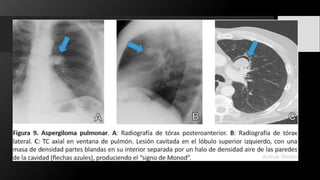

Aspergiloma. Un paciente varón de

58 años con sarcoidosis también

tenía fibrosis conocida desde hacía

mucho tiempo. La CXR de rutina

reveló opacidades en los segmentos

apicales de ambos pulmones. La TC

mostró un gran contenido de

quistes fibróticos conocidos

apicalmente con aire en forma de

media luna (flechas cortas) en la

parte anterior debido a grandes

bolas de hongos formadas (flechas

largas). Había engrosamiento

pleural local (flecha gruesa) (sin

síntomas).